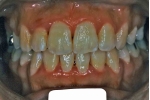

カテゴリー:ClassⅡ division 2 malocclusion (Overbite 5mm以上; 抜歯症例)

しかし、出題基準にも書いてあるように、このケースは欧米の白人によく見られるケースで、東洋人にはきわめて稀である。そこで類似ケースとして過蓋咬合(かがいこうごう)のケースを代替えとして認めるという配慮をしている。過蓋咬合とは非常に強く深く咬んでいる状態を言う。Overbiteとは前歯の垂直的な重なり具合を示す数値で、5mm以上だと上の前歯が下の前歯をほとんど覆い尽くしている感じになるので、前から見ると下の前歯はほとんど見えない状態になる。こういう状態が典型的な過蓋咬合である。典型的なclassⅡ,division 2のケースは過蓋咬合を合併している。

| 初診時